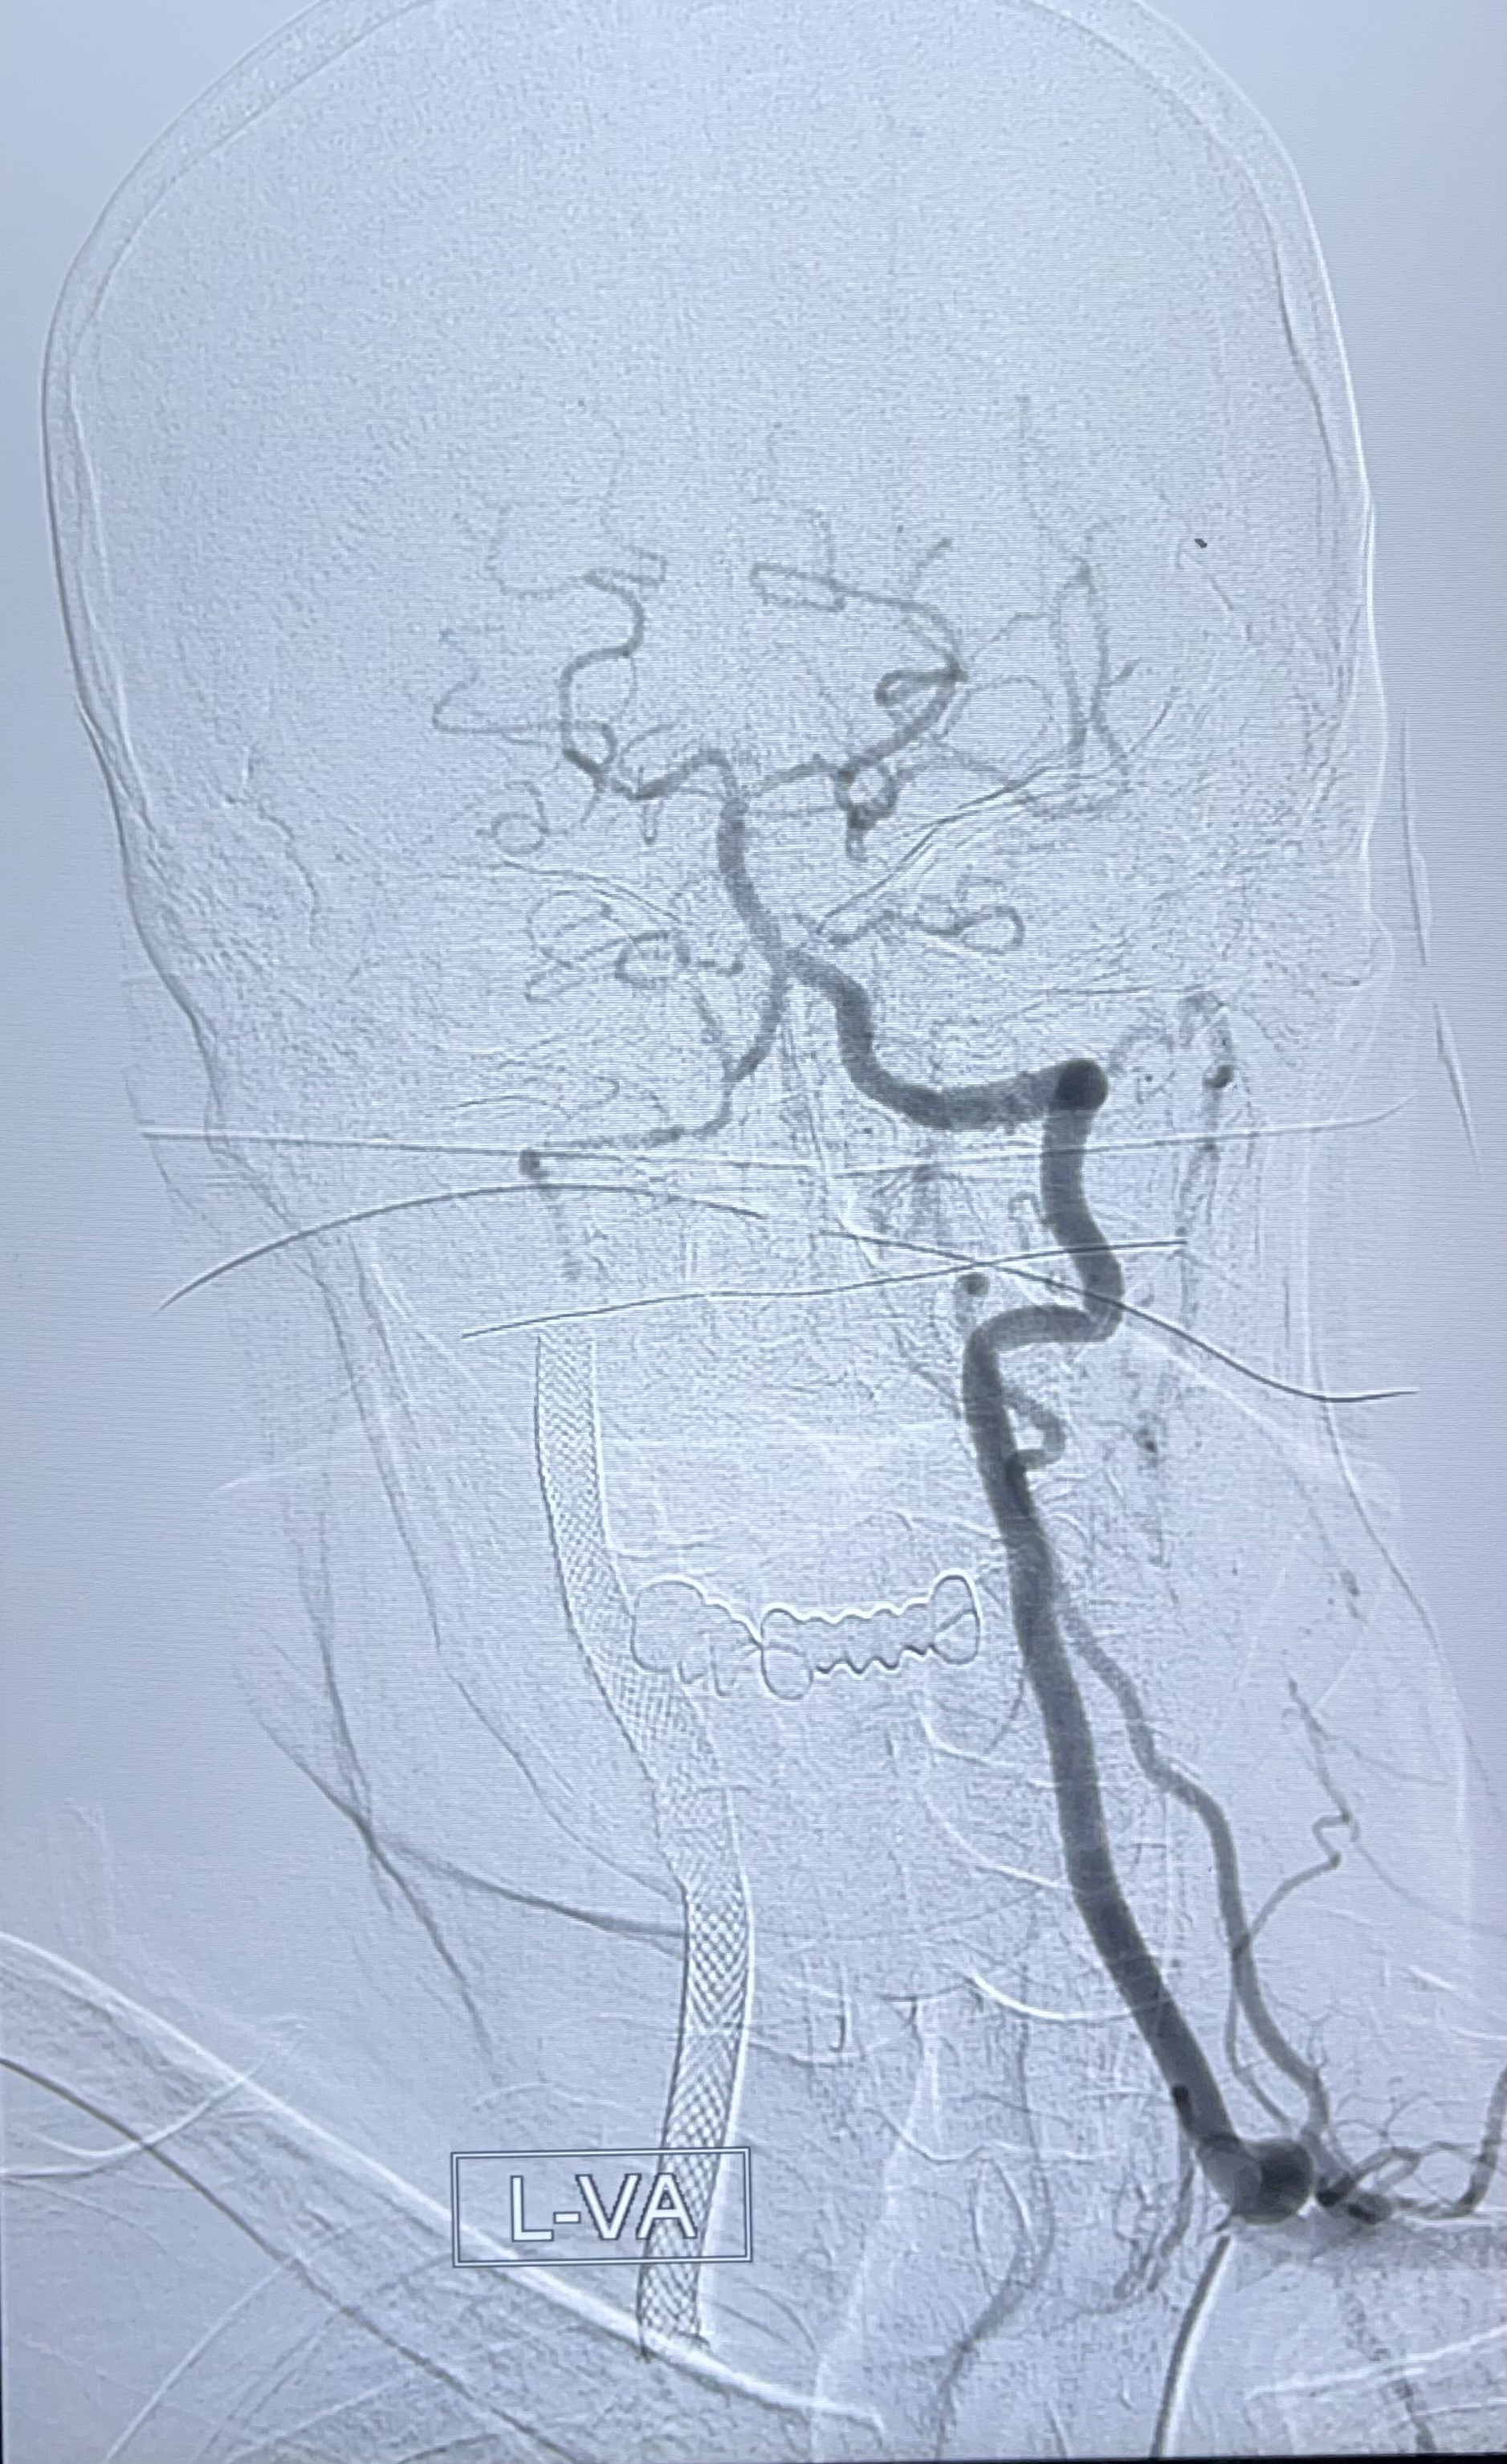

左侧椎动脉可见代偿显示左侧前循环

经导引导管造影显示支架远端颈内动脉不规则狭窄伴局部充盈缺损,同时行全身肝素化5ml

泄除球囊造影显示局部管腔扩张佳

即刻造影显示狭窄扩张佳

即刻造影显示支架贴壁佳